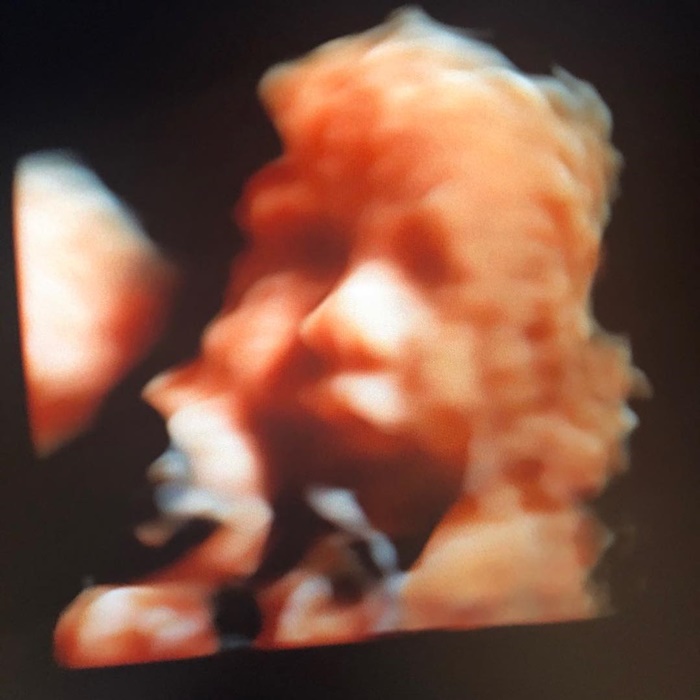

อีกไม่นานพิธีกรหนุ่ม อั๋น ภูวนาท ก็จะได้เป็นคุณพ่อเต็มตัวแล้ว เพราะภรรยาสาว จ๋า อลิสา ทายาททิฟฟานี่โชว์พัทยา ที่ตอนนี้กำลังตั้งครรภ์ได้ 8 เดือน ใกล้จะให้กำเนิดลูกชายคนแรกออกมาลืมตาดูโลกในอีกไม่นานนี้แล้ว

ล่าสุด (4 เมษายน 2561) อั๋น ภูวนาท ได้เผยคลิปวิดีโอสไตล์พ่อ-ลูกคุยกัน โดยเจ้าตัวกำลังทักทายลูกชายในท้องภรรยา ซึ่งขณะพูดคุยกันอยู่นั้น ท้องได้ขยับไปมาด้วย แต่งานนี้ไม่ใช่เพราะลูกดิ้น แต่เป็นเพราะสาวจ๋า ขำหนักมากด้วยความจั๊กจี้